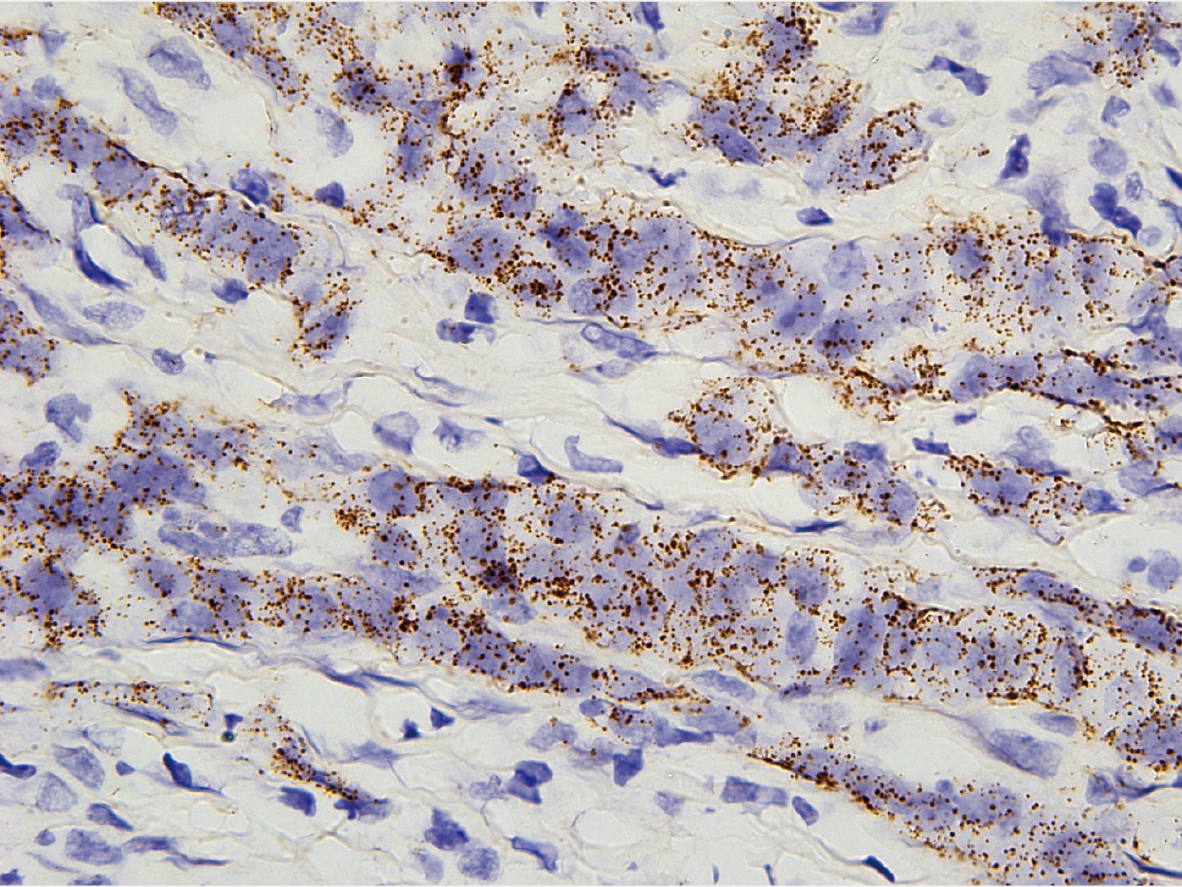

新型RNA原位测序技术发布!德运康瑞领跑单细胞与空间组学领域,临床潜力引关注!

德运康瑞CEO李嘉成主持了本次发布会,并在开场致辞中表示德运康瑞作为国内少有的专注于全链条单细胞与空间多组学技术的公司,通过底层技术的不断创新,致力于打造具有国际竞争力的单细胞和空间多组学产品管线。